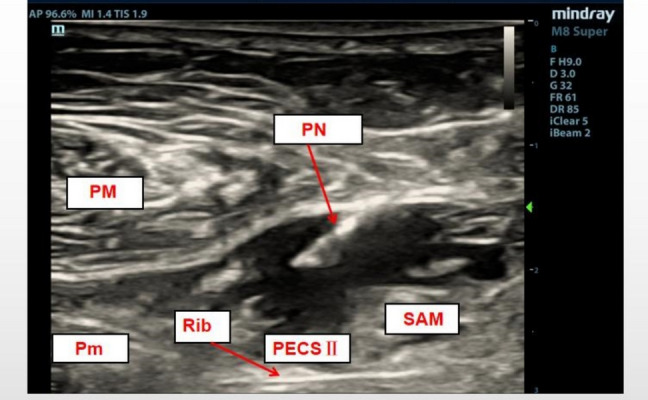

Background: Injury to the sternocostal joint during minimally invasive cardiac surgery frequently results in severe pain, yet there is no established standard for perioperative analgesia. This randomized controlled trial evaluated whether adding 1 μg/kg dexmedetomidine to 0.375% ropivacaine for chest wall fascial plane blocks enhances opioid sparing in ultra-fast-track (UFT) minimally invasive heart valve surgery.

Methods: Seventy-six elective patients were randomized (1:1) in a double-blind manner. The control group received 60 mL of 0.375% ropivacaine, while the DEX group was administered 60 mL of 1 μg/kg dexmedetomidine plus 0.375% ropivacaine. The primary outcomes were intraoperative remifentanil use and 24-h postoperative sufentanil consumption, which served as co-primary endpoints to evaluate opioid-sparing effects. Secondary outcomes included 24-h postoperative sufentanil consumption, 24-h oxycodone use, patient-controlled analgesia (PCA) activations, episodes of Visual Analog Scale (VAS) scores ≥ 3 within 48 h, time to recovery of consciousness, time to extubation, duration of intensive care unit (ICU), and hospital stays, and complications.